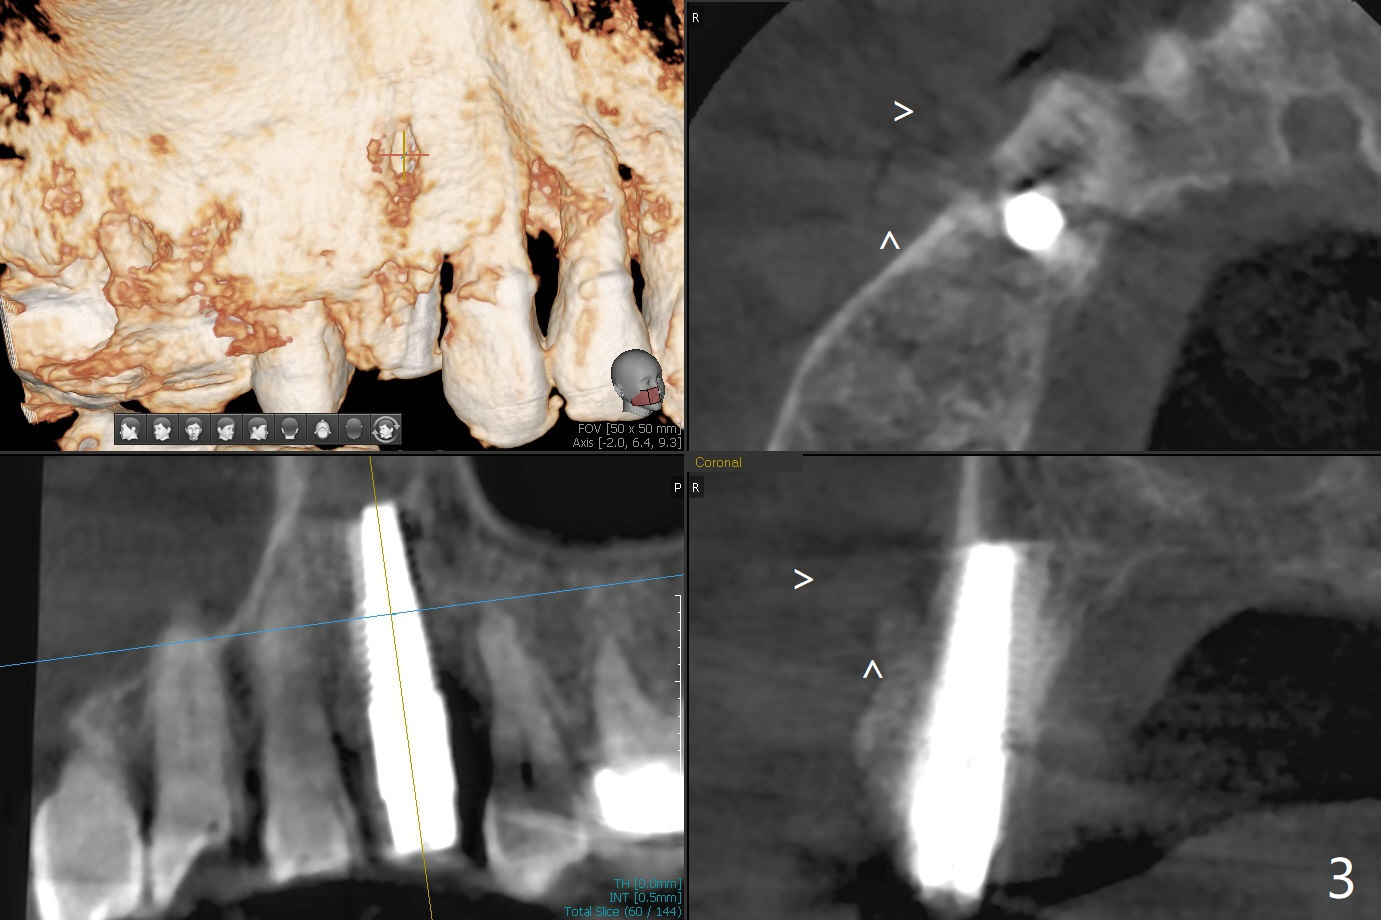

After extraction of the tooth #4 with fistula (Fig.1), the buccal bony defect is superior to the fistula. Before placement of a 4.5x17 mm tissue-level implant (Fig.2) and after osteotomy for bone-level one, PRF and mixture of autogenous bone and allograft are pushed from the socket through the buccal defect for repair (Fig.3 arrowheads). The trajectory of the implant (Fig.4) is consistent with design (Fig.5). The fistula reduces in size and in redness, while the apical elevation (as related to the underlying bone graft) remains prominent 13 days postop (Fig.6,7 *). The distal defect has been apparently repaired 9 months postop (Fig.8 *, as compared to immediately post bone graft in Fig.2). The distal defect has been apparently repaired 9 months postop (Fig.8 *, as compared to immediately post bone graft in Fig.2). The fistula disappears (Fig.9).